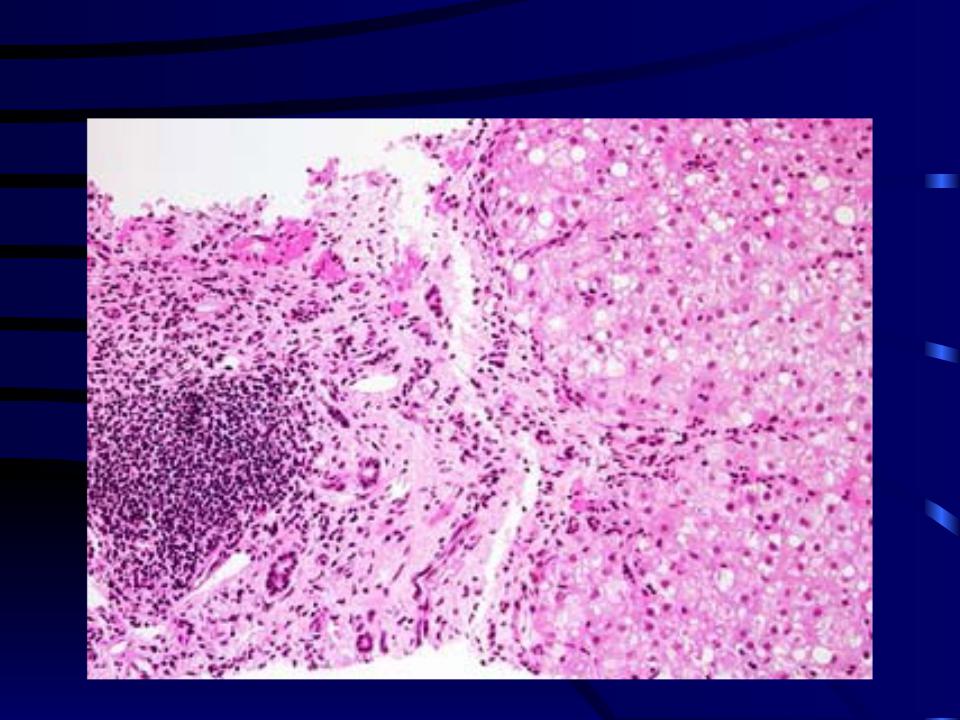

Микроскопический взгляд на мишитарный туберкулез легкого: фотодокументация

Раздел: Снимки-откровения